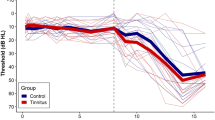

Global parameters

Overall, there were no significant between-group differences in any of the global parameters tested in this study. Table 2 and Fig. 2 summarize the several measures of small-world networks in the two groups, including Cp, Lp, Eg and Eloc. Figure 3 shows the changes in these four parameters as a function of sparsity in the range between 0.05 and 0.5. The curves from the two groups overlapped with each other. The two measures of small-world efficiencies were also identical in the two groups, with almost identical path lengths (λ ≈ 1) and high clustering coefficients (γ > 1).